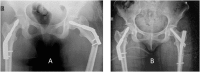

A 27 years old sedentary woman presented bilateral femoral neck stress fractures after having clinically recovered from anorexia nervosa and was treated with bilateral internal fixation.

Conclusion: Although light exercise is usually considered after recovery from anorexia nervosa to improve bone quality, this case of a sedentary patient suggests that weight gain, per se, could increase the stress fracture risk. Because of the physiological and psychological characteristics, these patients should be treated with a multi-disciplinary approach.